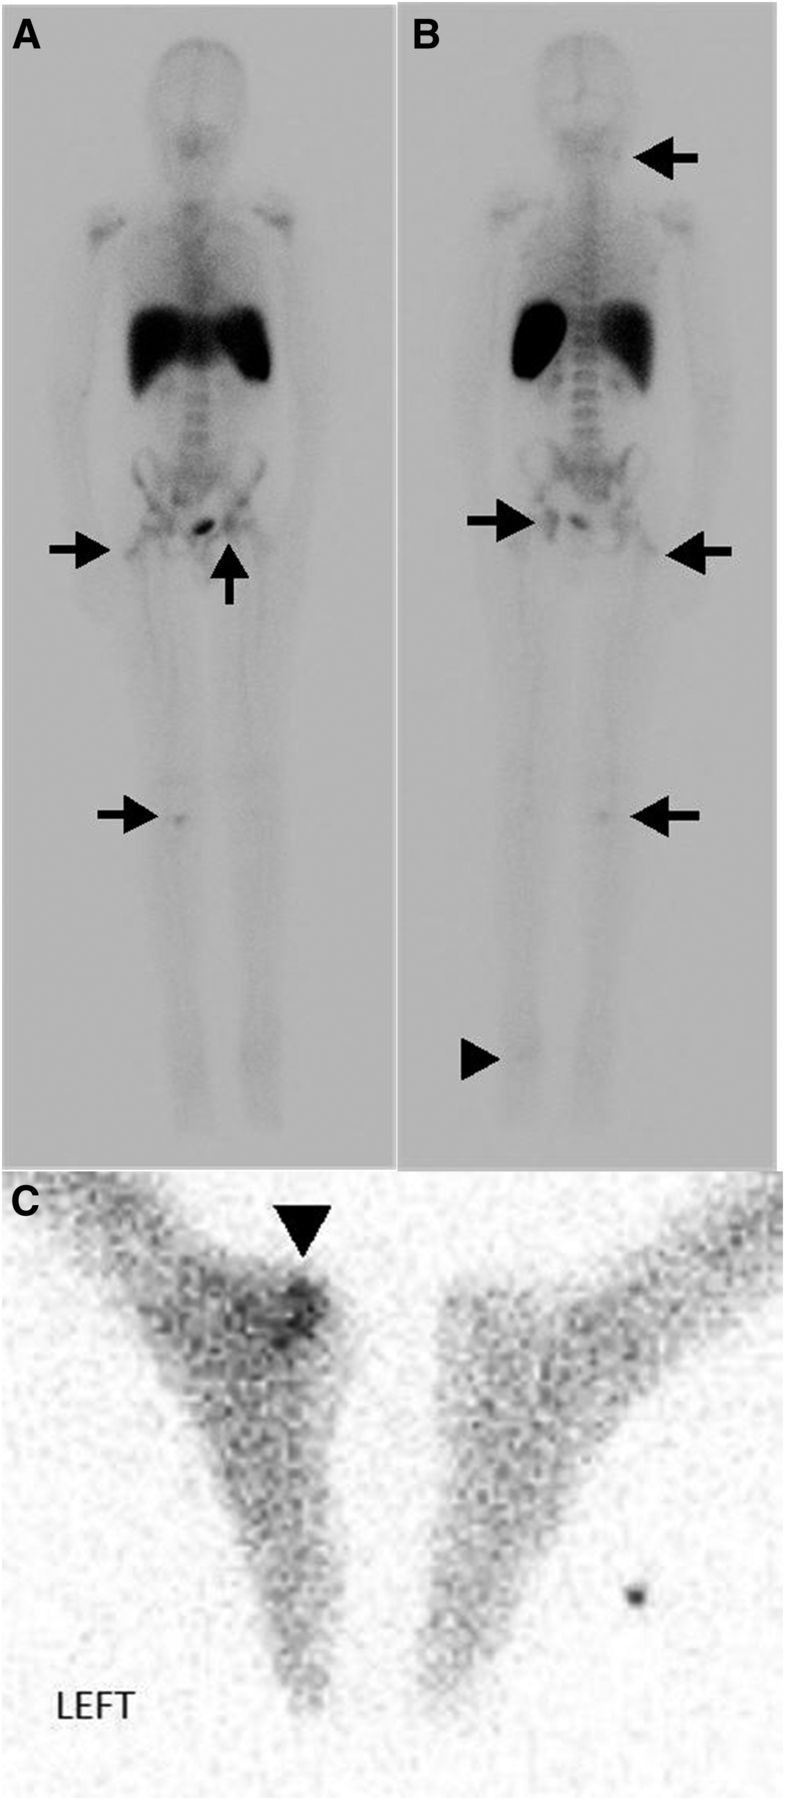

Figure 1 from Use of indium 111labeled white blood cell scan in the Labeled White Blood Cell Scan A labelled white cell scan is used to show areas of infection or inflammation (swelling) within the body. A radioactive scan detects abscesses or infections in the body by using a radioactive material. A 111 indium white blood cell scan, also known as a wbc scan, is a diagnostic imaging test that uses a special radioactive substance to. The scan. Labeled White Blood Cell Scan.